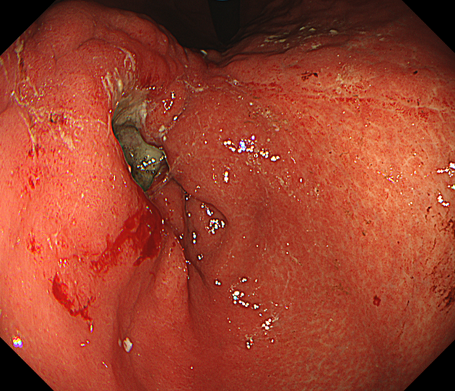

胃潰瘍とは、胃の粘膜に炎症が起きて、深い傷(潰瘍)ができている状態を指します。

主な症状は腹痛と出血になります。

出血は吐血(コーヒー様の嘔吐物)と下血(黒色便)に分けられます。

• 内視鏡検査

内視鏡検査で出血が確認できれば止血処置を行うこともあります。止血困難な出血がある場合は手術が必要となることもあります。